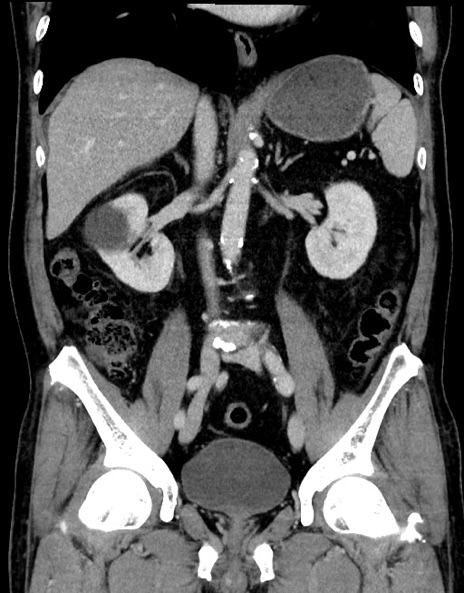

症例15(冠状断像)

【症例】70歳代男性

【主訴】腹痛

【現病歴】今朝から腹痛あり。全体的に痛い。特に左上の方。排ガスが今日はない。冷や汗が出る。

【既往歴】直腸癌術後

【身体所見】左側腹部〜上腹部に圧痛あり。腹膜刺激症状明らかなではない。軽度反跳痛。左下腹部に術後瘢痕あり。

【データ】WBC 7700、CRP 0.02